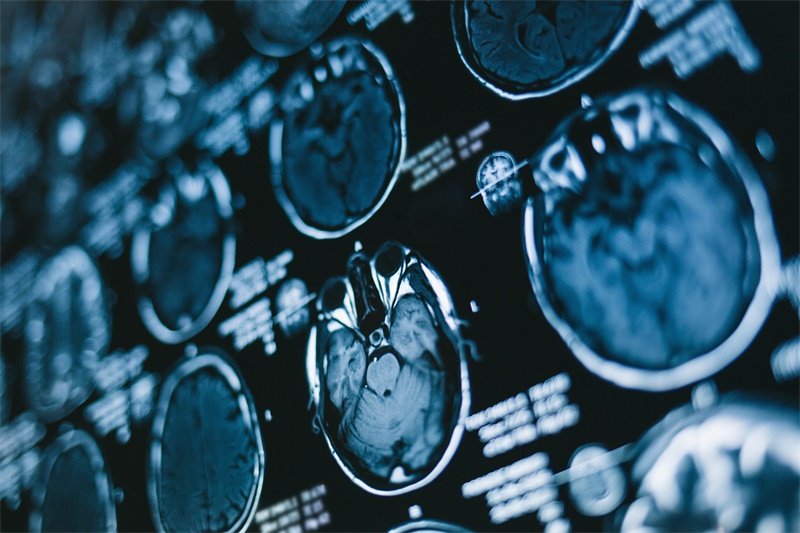

影像学检查在诊断中起关键作用。磁共振成像(MRI)是首选方法,它能清晰显示椎管内软组织病变,准确呈现占位病变的位置、大小、形态,以及与周围脊髓、神经根的关系。CT检查则更擅长展示椎管的骨性结构,帮助医生判断病变是否对骨质造成破坏。两种检查方法优势互补,具体如下表: